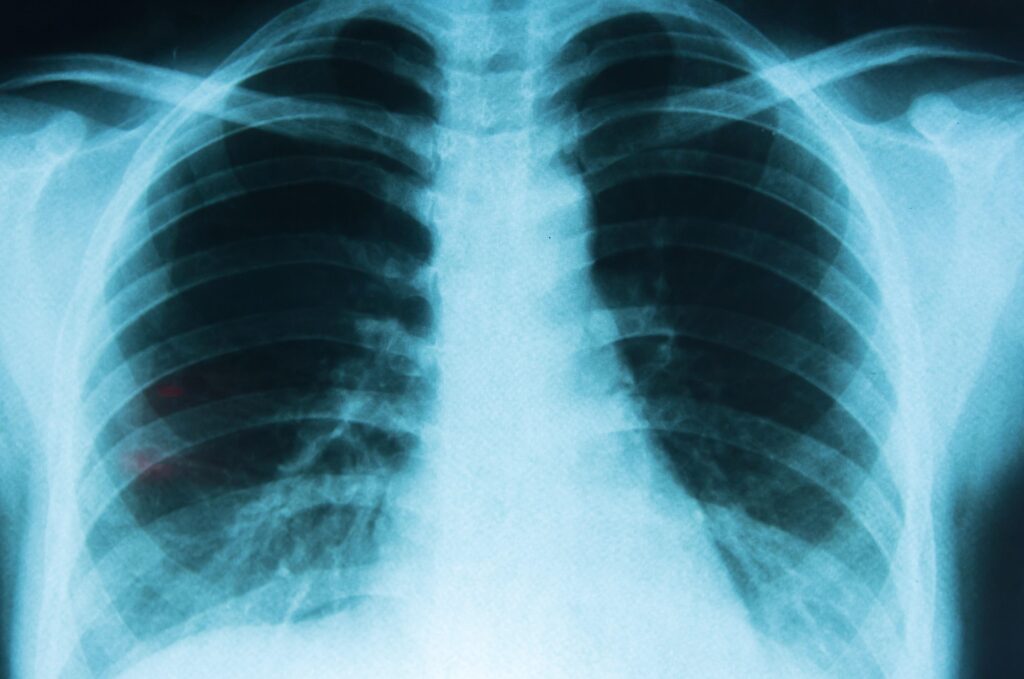

El Día Mundial del Cáncer de Pulmón se conmemora este lunes y los especialistas advierten que esta enfermedad sigue siendo una de las principales causas de muerte en el mundo, ya que según la Organización Mundial de la Salud (OMS) provoca entre 1,8 y 2,2 millones de muertes por año, lo que equivale al 20% de todos los fallecimientos por cáncer.

En Argentina, ocupa el segundo lugar en incidencia y el primero en mortalidad oncológica: se registran cerca de 12.000 nuevos diagnósticos y alrededor de 10.000 muertes anuales, lo que representa el 15% de todos los fallecimientos por cáncer.

En sus etapas iniciales, el cáncer de pulmón suele no presentar síntomas, lo que explica que muchos casos se diagnostiquen en fases avanzadas. Sin embargo, existen señales que pueden servir como alerta temprana y motivar la consulta médica.

Entre los síntomas más frecuentes se encuentran la tos persistente o que empeora con el tiempo, la presencia de sangre en la flema, el dolor torácico que aumenta al respirar profundo o toser, la ronquera y la dificultad para respirar. También pueden aparecer pérdida de peso o de apetito sin causa aparente, cansancio extremo y episodios repetidos de bronquitis o neumonía.

“Sabemos que el cáncer de pulmón muchas veces no produce síntomas hasta estadios tardíos. Por eso, recurrir a herramientas de diagnóstico como el tamizaje es clave para detectarlo a tiempo, especialmente en personas con factores de riesgo o antecedentes de exposición al tabaco”, explica Bugarín.

Dentro del tamizaje, la herramienta más utilizada es la tomografía computada de baja dosis (TCBD), un estudio rápido, sin dolor y de alta precisión que permite detectar lesiones pulmonares muy pequeñas, incluso antes de que aparezcan síntomas.